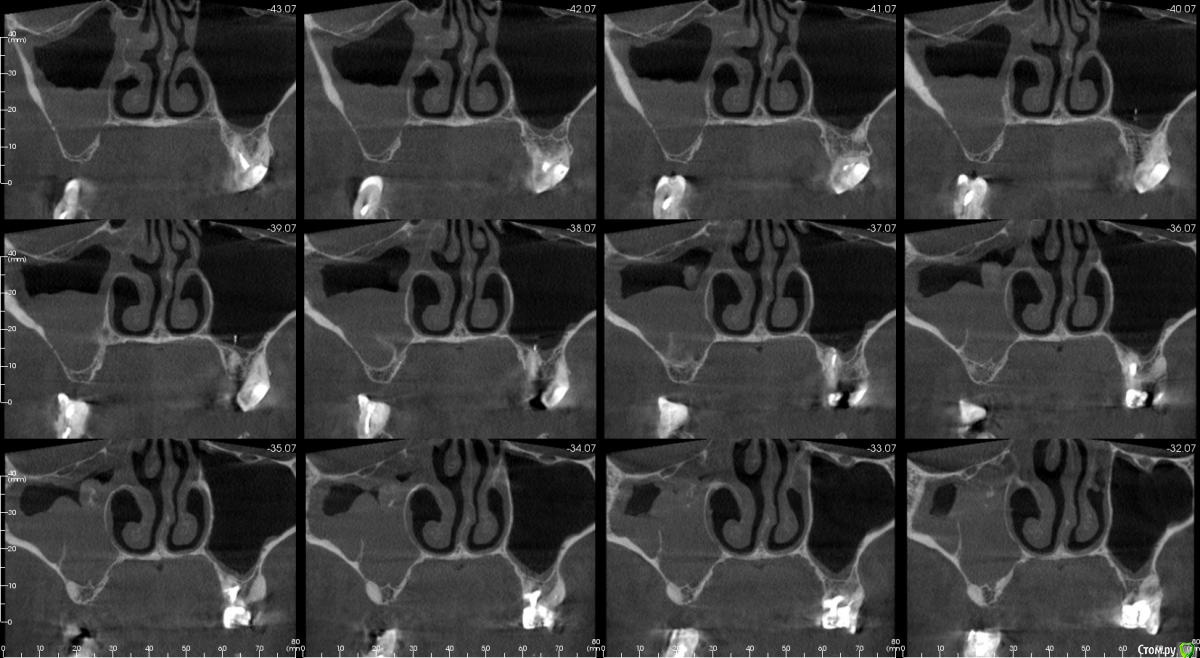

kamranchick Опубликовано 16 апреля, 2018 Автор Поделиться Опубликовано 16 апреля, 2018 Смотрел, и такое заключение дал. вот меня и смутило, в верхней трети около соустя вообще вкрапления какие то есть )) Ссылка на комментарий

Irouil Опубликовано 16 апреля, 2018 Поделиться Опубликовано 16 апреля, 2018 Смотрел, и такое заключение дал. вот меня и смутило, в верхней трети около соустя вообще вкрапления какие то есть ))Больше всего похоже на грибковое тело, и вкрапления эти намекают, и контуры затенения. Пунктировать не стал ЛОР это? 1 Ссылка на комментарий

kamranchick Опубликовано 16 апреля, 2018 Автор Поделиться Опубликовано 16 апреля, 2018 Больше всего похоже на грибковое тело, и вкрапления эти намекают, и контуры затенения. Пунктировать не стал ЛОР этоОтправил для санации, он написал вот это только( что ретенционная, но потом я внимательно начал крутить туда сюда и вот засомневался Ссылка на комментарий